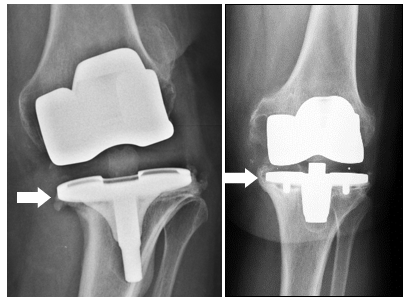

LES RAISONS COURANTES pour remplacer une prothèse de genou incluent, outre l’infection, l’instabilité ou la douleur persistante.

LORS D'UNE NOUVELLE OPÉRATION DU GENOU, des implants spéciaux sont souvent nécessaires pour remplacer les ligaments défectueux (avec une prothèse dite couplée) ou pour RECONSTRUIRE LES DÉFAUTS DE L'OS (avec des augmentations ou du MATÉRIEL de remplacement osseux).